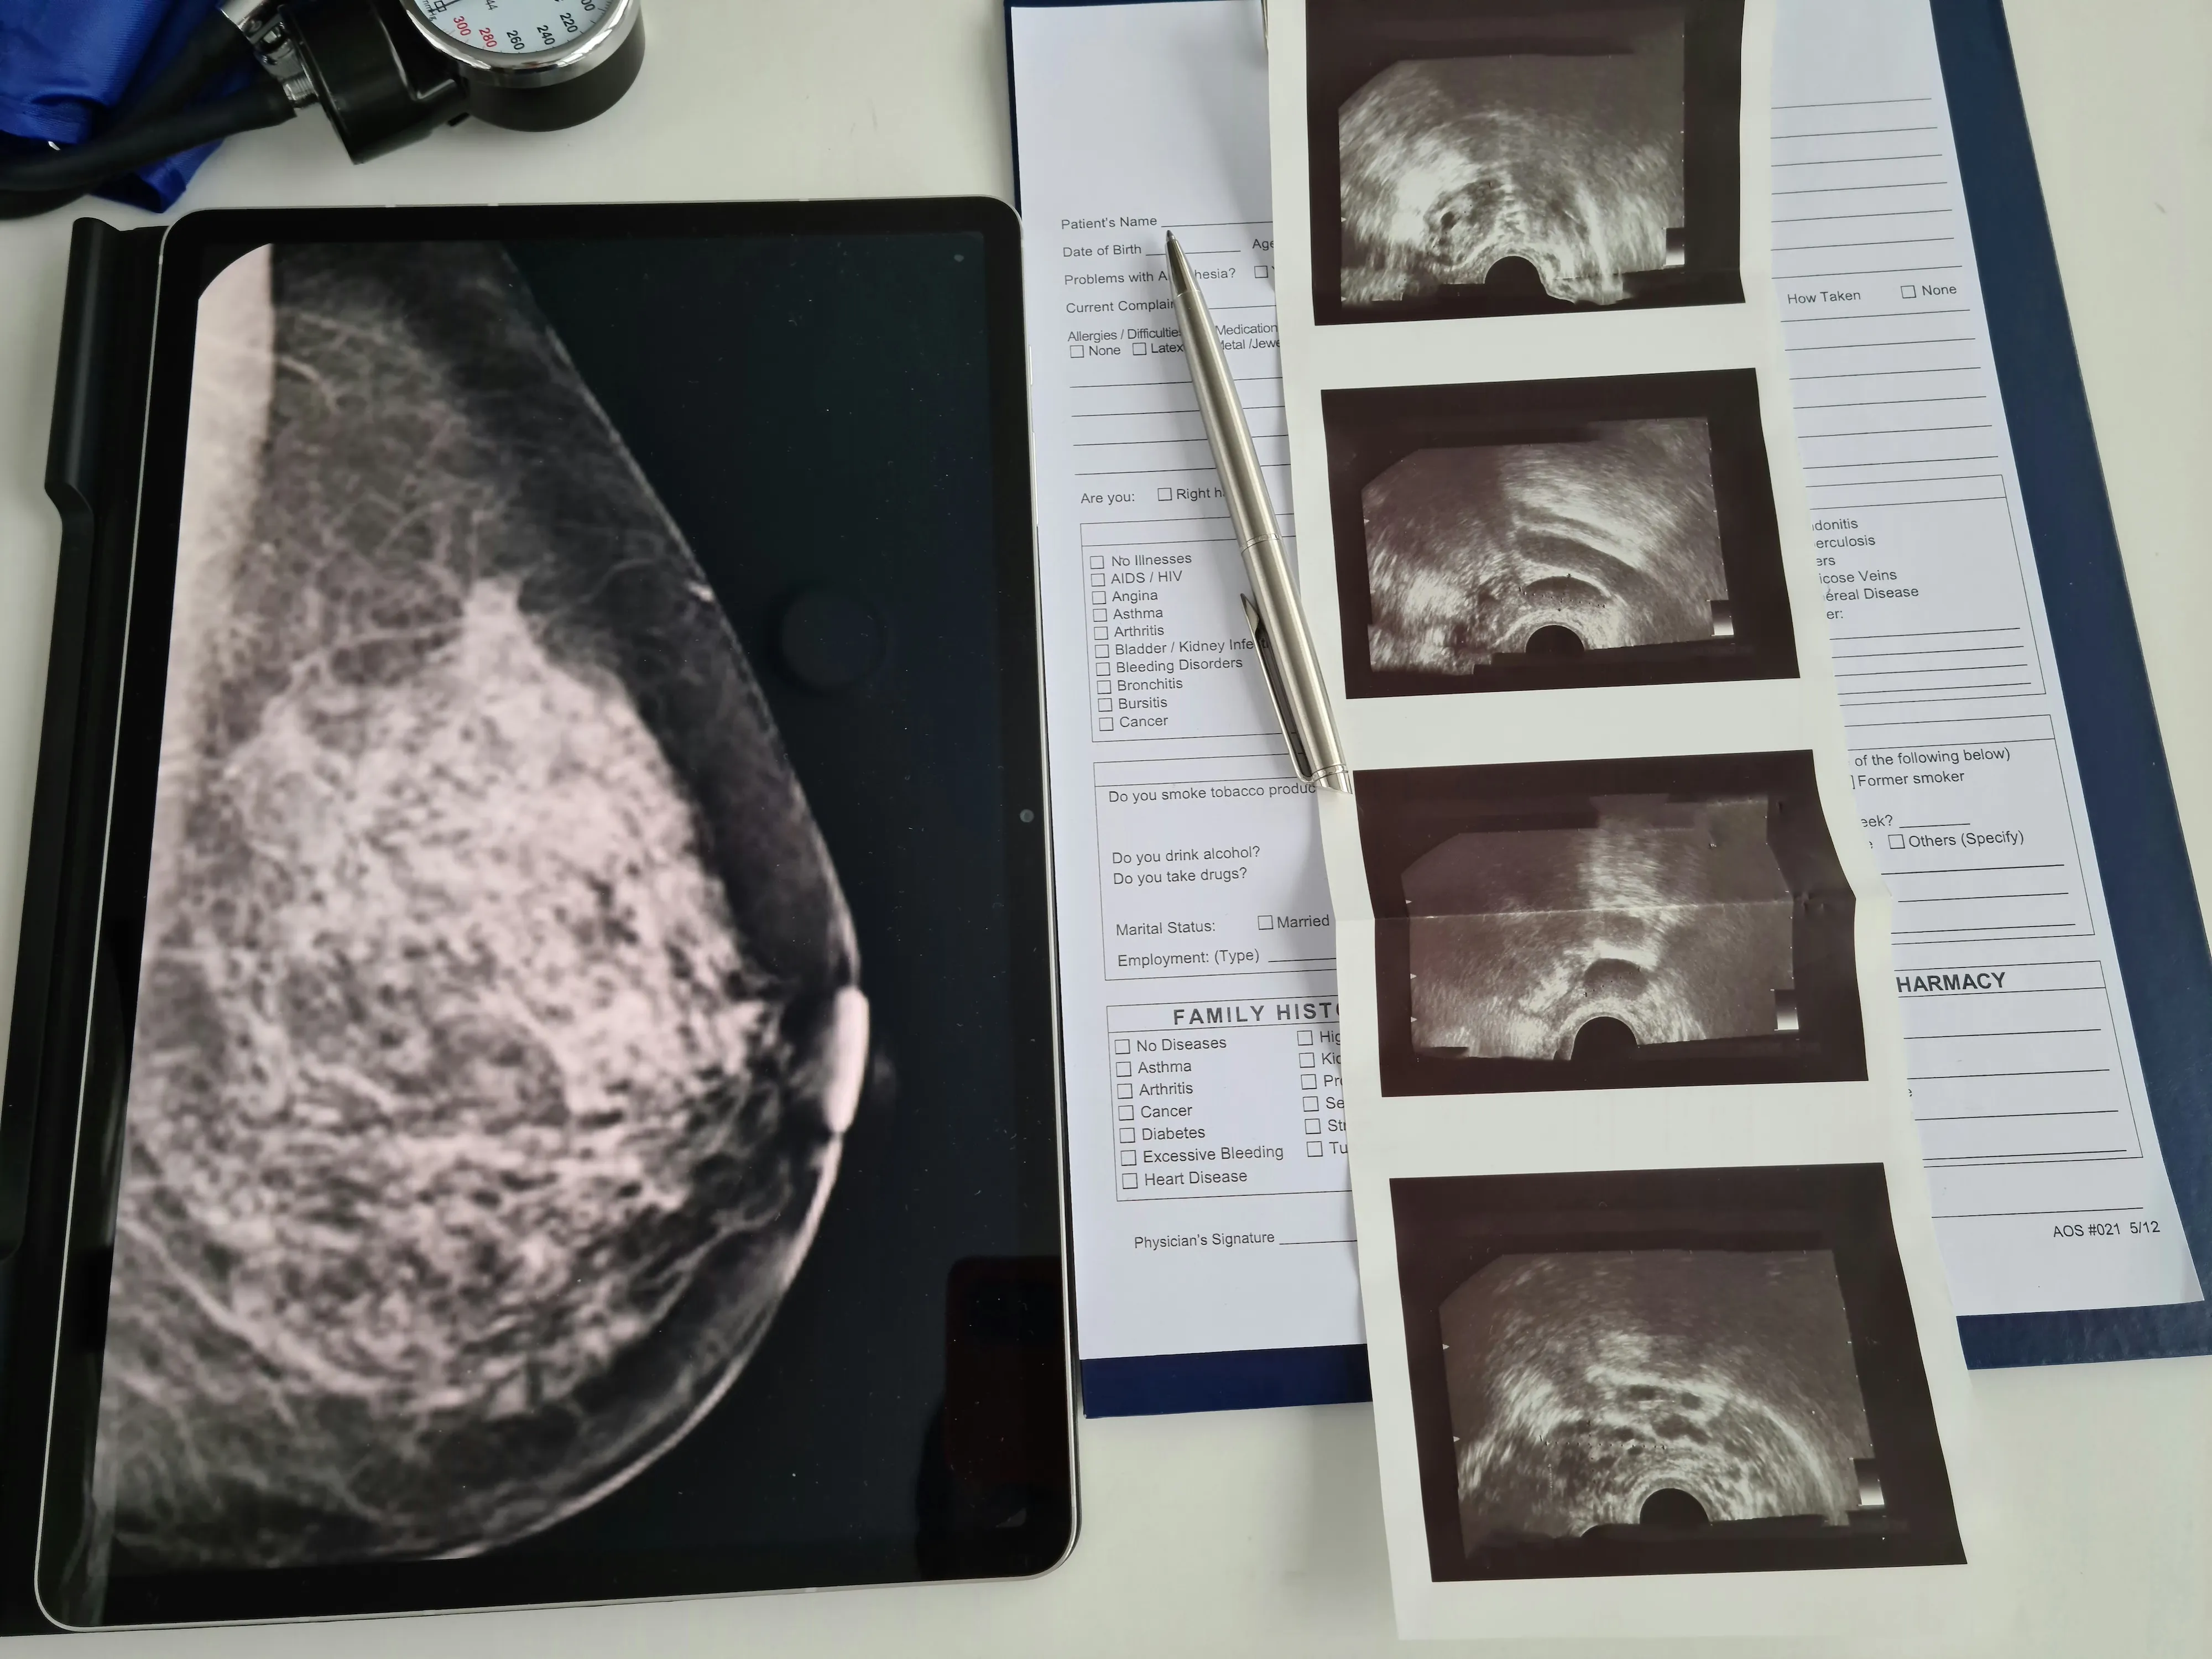

For over 60 years, mammograms have helped catch cancer early. But they’ve never been able to tell someone who appears perfectly healthy that they may be at higher risk in the future. That changes now.

Clairity partnered with KUNGFU.AI to build and train a groundbreaking AI model on over half a million mammograms. The result is the first FDA-authorized AI platform that can predict a woman’s five-year risk of developing breast cancer using only a standard screening mammogram.

To be clear, this model doesn’t detect cancer. It predicts risk before any signs of cancer appear. This is a leap beyond traditional detection tools, and far more challenging to pull off.

We validated the model on 77,000 mammograms from five different sites across the country, each with real five-year patient outcomes. It delivered a step-function improvement in predictive accuracy, something the field has been chasing for decades.